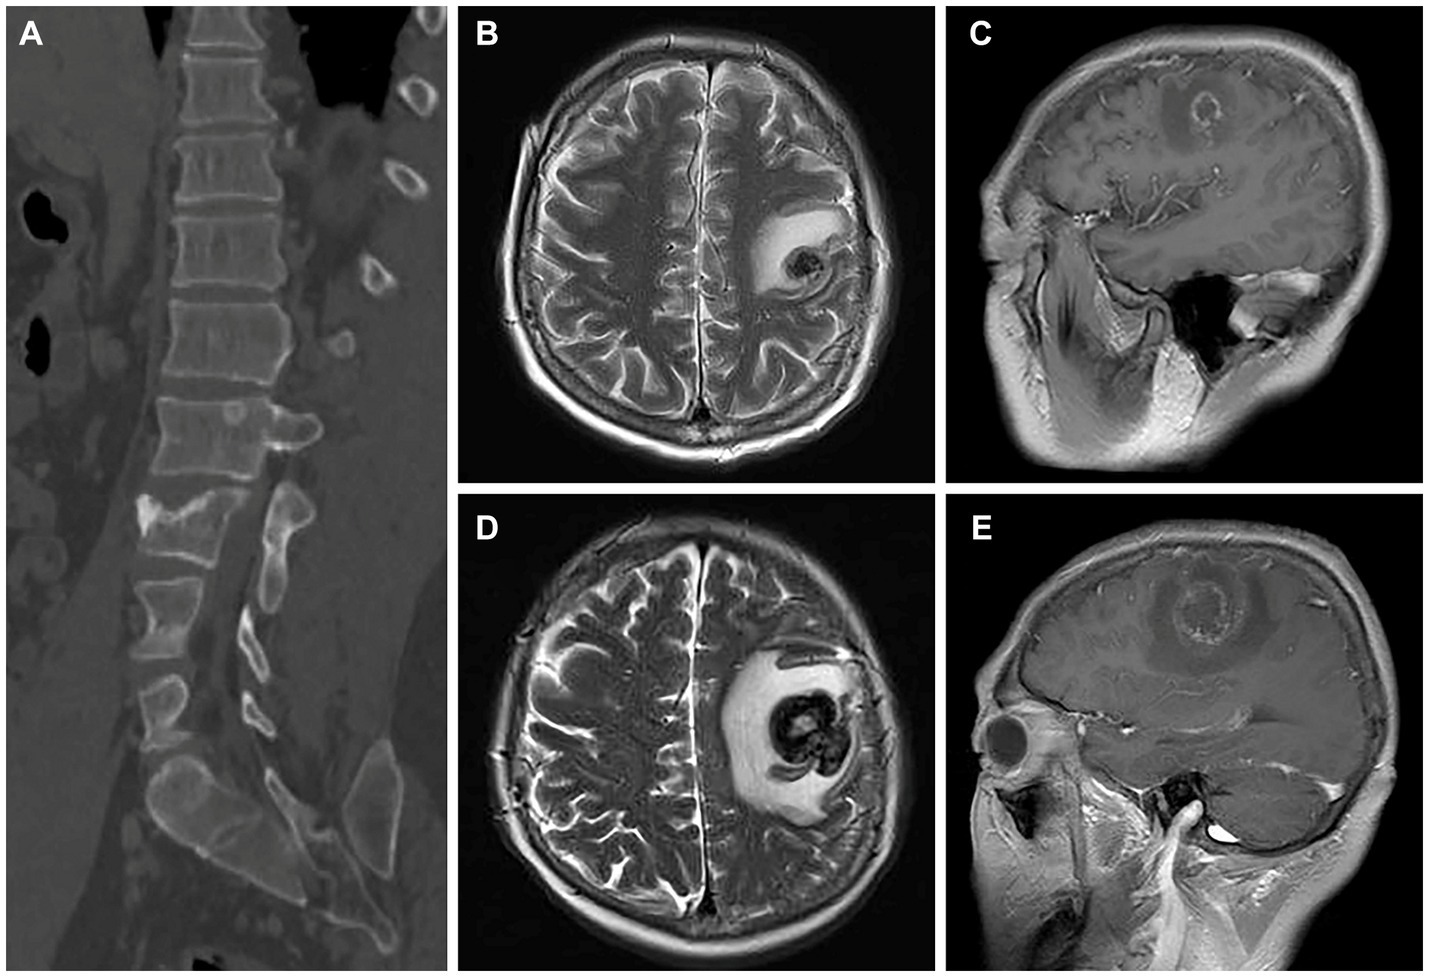

After confirming the absence of contraindications to chemotherapy, the patient underwent treatment with an eight-cycle regimen consisting of etoposide (200 mg/d1–4), cisplatin (40 mg/d1–3), and bleomycin (30 U/d1,5). According to RECIST guidelines, subsequent CT examinations indicated stable disease (SD) in the patient’s status. Considering the patient’s chemotherapy tolerance, a collaborative decision was made to initiate a four-cycle course of anti-tumor therapy using the PD-1 antibody (pembrolizumab). Unfortunately, the patient experienced adverse effects of diarrhoea during this treatment phase. At the conclusion of the Avelumab treatment, follow-up CT scans revealed an increase in size of metastatic lesions in both lungs and liver, accompanied by the emergence of multiple metastases in the vertebral body (Figure 4A). Due to an inadequate response to pembrolizumab, the patient was subsequently treated with the regimen of “methotrexate (1.5 g) + actinomycin (0.4 mg).” Two weeks post-treatment initiation, the patient presented with dizziness and headache. A cranial MRI disclosed a rounded lesion in the left frontal lobe with high signal on T2WI (Figure 4B), measuring approximately 1.7 cm in diameter, and exhibiting inhomogeneous annular enhancement (Figure 4C). Nine days later, the patient’s secondary epileptic symptoms exacerbated, with a repeat MRI showing an enlarged frontal lobe lesion surpassing its previous size (Figure 4D). Additionally, new bilateral occipital lobe metastases were evident (Figure 4E). Despite medical recommendations, the patient declined further treatment and succumbed to the illness 2 weeks later. The patient’s overall survival was a mere 5 months following diagnosis.

Figure 4

CT images and magnetic resonance images after treatment for choriocarcinoma (May 5 & 14, 2020). (A) The sagittal bone window CT image reveals multiple metastases in the vertebral body. (B,C) The T2-weighted imaging (T2WI) and enhanced images indicate the development of brain metastases in the patient. (D,E) Subsequent scans after 9 days demonstrate an enlargement and increased size of the patient’s brain metastatic lesions compared to the previous images in both T2WI and enhanced sequences.